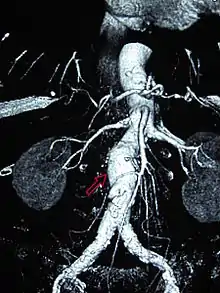

CT reconstruction image of an abdominal aortic aneurysm

A 6.5 cm AAA with a 3 cm lumen